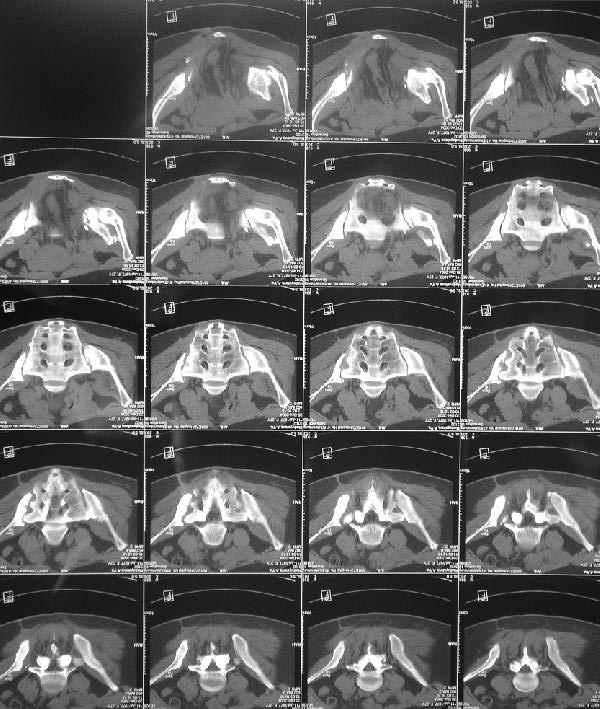

Картина на сегодня:

В настоящее время больная ходит без дополнительной опоры, боль в области таза не беспокоит, неудобств при сидении не испытывает, свободно проходит расстояние в 2-3км. Отмечается незначительная хромота, периодические боли в поясничной области низкой интенсивности, не требующие приема медикаментов, кроме того имеется вагинальный импинджемент. Срок после операции 1 год и 2 месяца.Было бы интересно услышать ваши комментарии. С уважением Агалаков М.В.